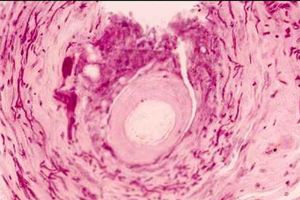

口腔念珠菌病是真菌——念珠菌属感染所引起的口腔粘膜疾病,它对患者的健康的影响是很大的,但是也有些疾病与其症状相似,因此需要加以鉴别,那么口腔念珠菌病的鉴别诊断有哪些呢?